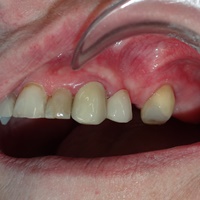

Pacjent z rozległa torbielą 21, 22. Po przygotowaniu endodontycznym wykonano zabieg resekcji. Na uwagę zasługuje delikatne wykonanie zabiegu - na błonie śluzowej i dziąsłach nie sa widoczne blizny pozabiegowe, co jest bardzo ważne u pacjenta z wysoka linią uśmiechu.